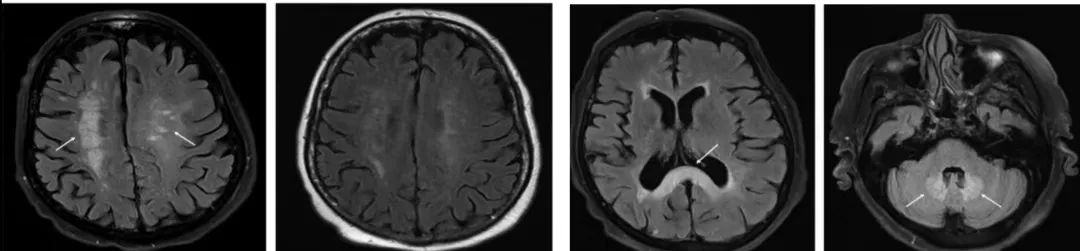

答案:肥大性下橄榄核变性(HOD)。

注:图左侧为患者复诊MRI放大图,右侧示齿状核—红核—橄榄核通路即Guillain‐Mollaret 三角。

完整的Guillain‐Mollaret 三角由一侧齿状核、对侧红核和对侧下橄榄核组成。齿状核的神经纤维经小脑上脚,交叉后到达对侧红核,红核发出的神经纤维到达同侧的下橄榄核,下橄榄核再发出神经纤维经小脑下脚到达对侧小脑皮质,继而投射到小脑齿状核。肥大性下橄榄核变性(HOD)的发病机制主要是齿状核—红核—橄榄核环路的破坏,常见的病因有海绵状血管瘤、手术、出血、梗死、肿瘤、外伤、炎症、脱髓鞘、变性疾病及放射性损伤等。原发病灶常位于中脑、脑桥或小脑。脑梗死是 HOD 的常见病因。HOD最核心的临床特点:Guillain‐Mollaret 三角上的原发病变(DTI和DTT可显示格莫三角环路破坏)、迟发性特征性症状(如腭肌阵挛、眼震、复视、共济失调、肢体阵挛等)、下橄榄核增大且T2WI、FLAIR序列上呈高信号。当 Guillain‐Mollaret 三角受损之后,下橄榄核的神经元失去了上游神经元的抑制从而出现异常活动,患者常表现出腭肌阵挛、眼震、复视、共济失调、肢体阵挛等特征性症状。腭肌阵挛是 HOD 的代表性体征,但并非出现在所有病例中。